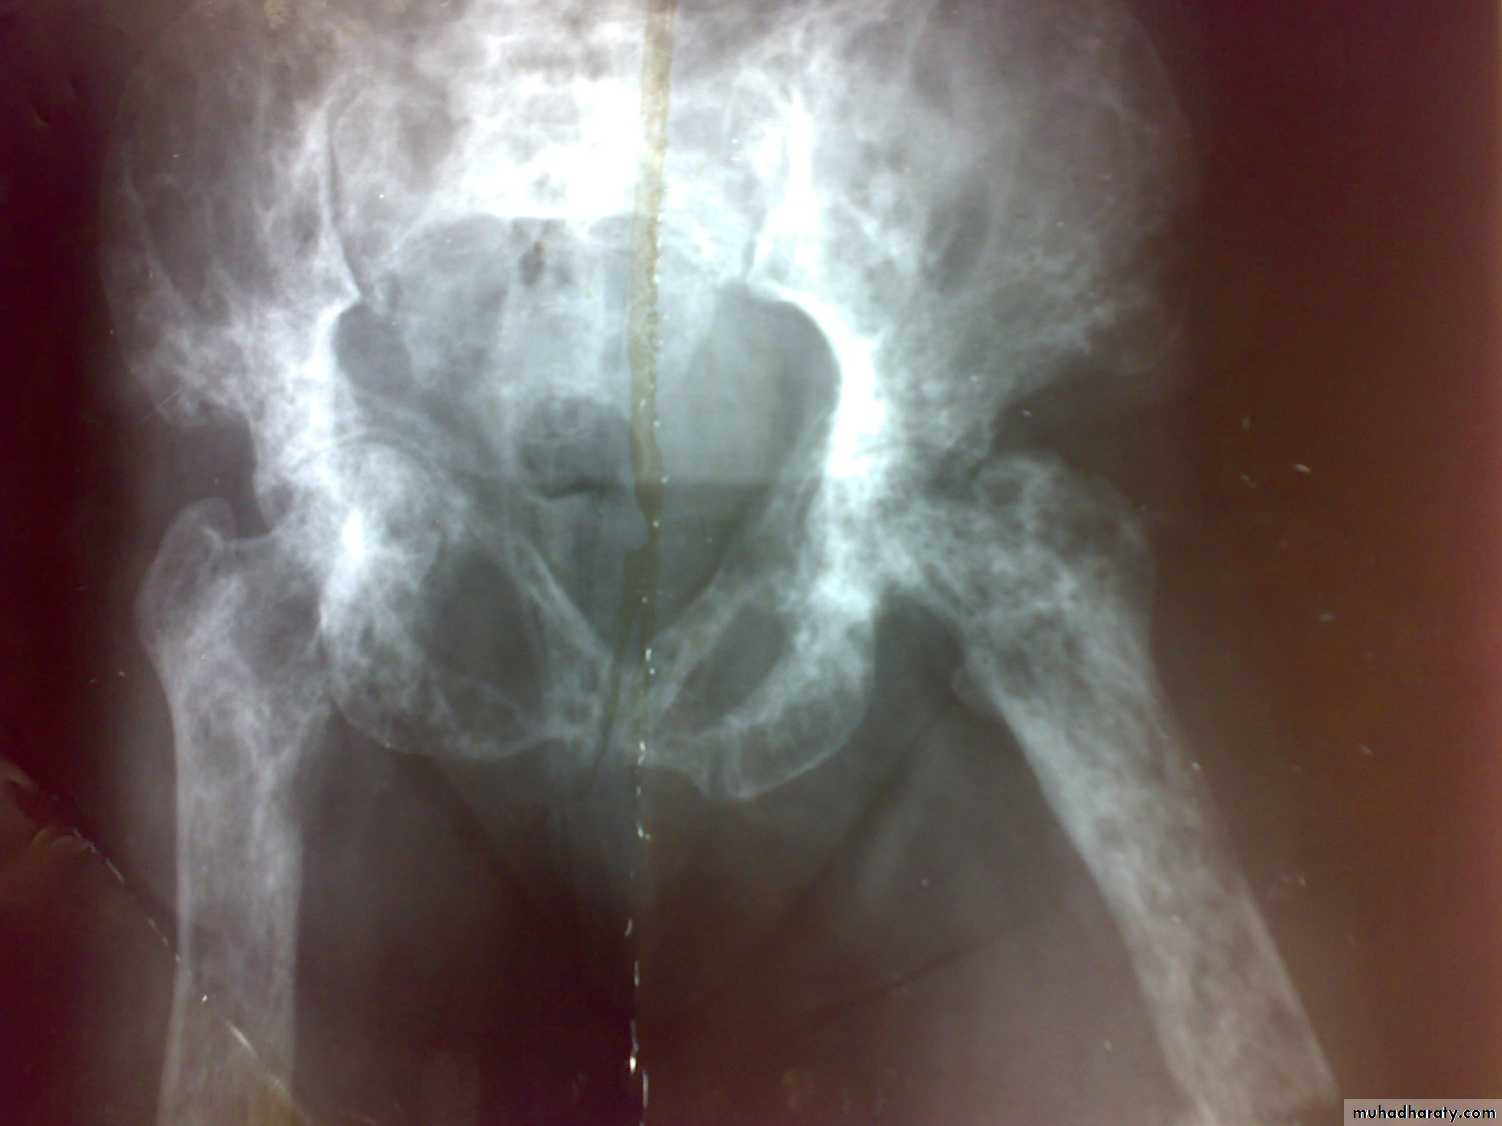

OSTEOPOROSIS Reduction of normally mineralized bone mass per volume.

It is a clinical disorder characterized by an abnormally low bone mass and defects in bone structure, render the bone fragile.

A state in which bone is fully mineralized but its structure is abnormally porous and its strength is less than normal person of that age and sex

Osteopenia: bone which appears to be less dense than normal X-ray.

4- Osteoporosis is common cause of fractures especially femoral neck fractures , vertebral fractures and distal radial fractures .